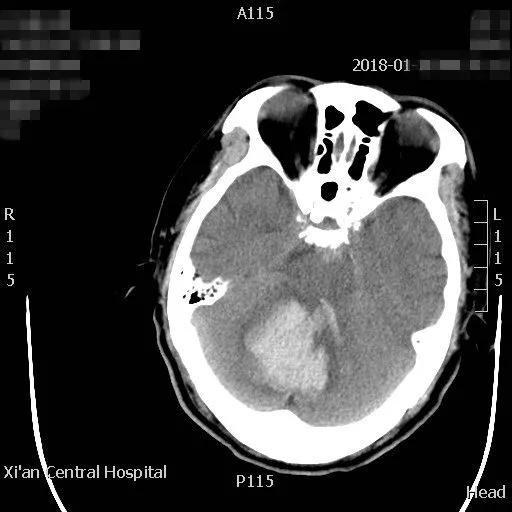

近日,一位六十岁的男性,在家中突发头痛、呕吐、左侧肢体瘫软无力摔倒在地,被家人急送按摩视频 急诊科,急诊接诊后发现患者处于昏迷状态,遂急查颅脑CT并请神经外科会诊。CT结果显示患者小脑出血40毫升,即刻收住神经外科住院。

患者病情危重,出血点位于后颅窝靠近天幕,位置狭小、深在、靠近脑干、直视困难,应用普通手术操作困难,容易损伤脑干,血肿也不容易彻底清除。主管主任医师王占尧对该患者进行了详细的查体后,与治疗小组商议手术方案。为进一步减少小脑皮层损伤、降低颅脑创伤,王占尧主任医师决定对该患者使用内镜辅助清除血肿。